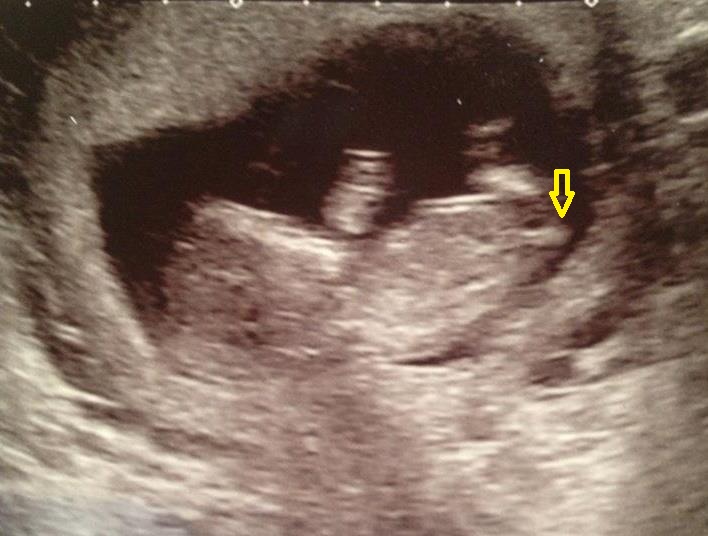

hiya is this my babys nub?.....if not what is it and can anyone tell me where to look for one and what they look like lol im rubbish at this.... :) xx

no thats too low down to the nub in my opinion and points down (boys are angled up, girls are parrellel). I think that is part of either the hip or the leg.

I could be wrong as pic is blurry but i can't see a nub in this pic, do you have any more?

Also, how far along is the baby, he/she only looks small (although it could just be the pic or angle)

mrs p thanks for your reply, this pic was at 12+5 ... was so dissapointed with the pic she printed off we saw the baby so much clearer than this :( hope we dnt get her for our 20 week scan! xx